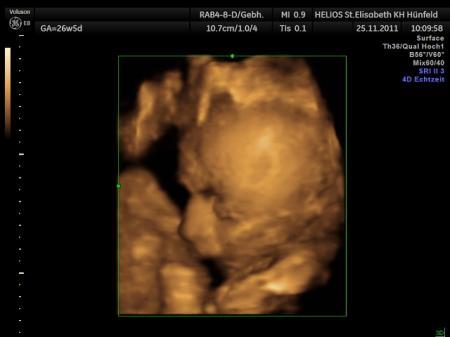

Bild zu Mir ist jetzt voll schlecht :D - Forum für Februar - Mamis